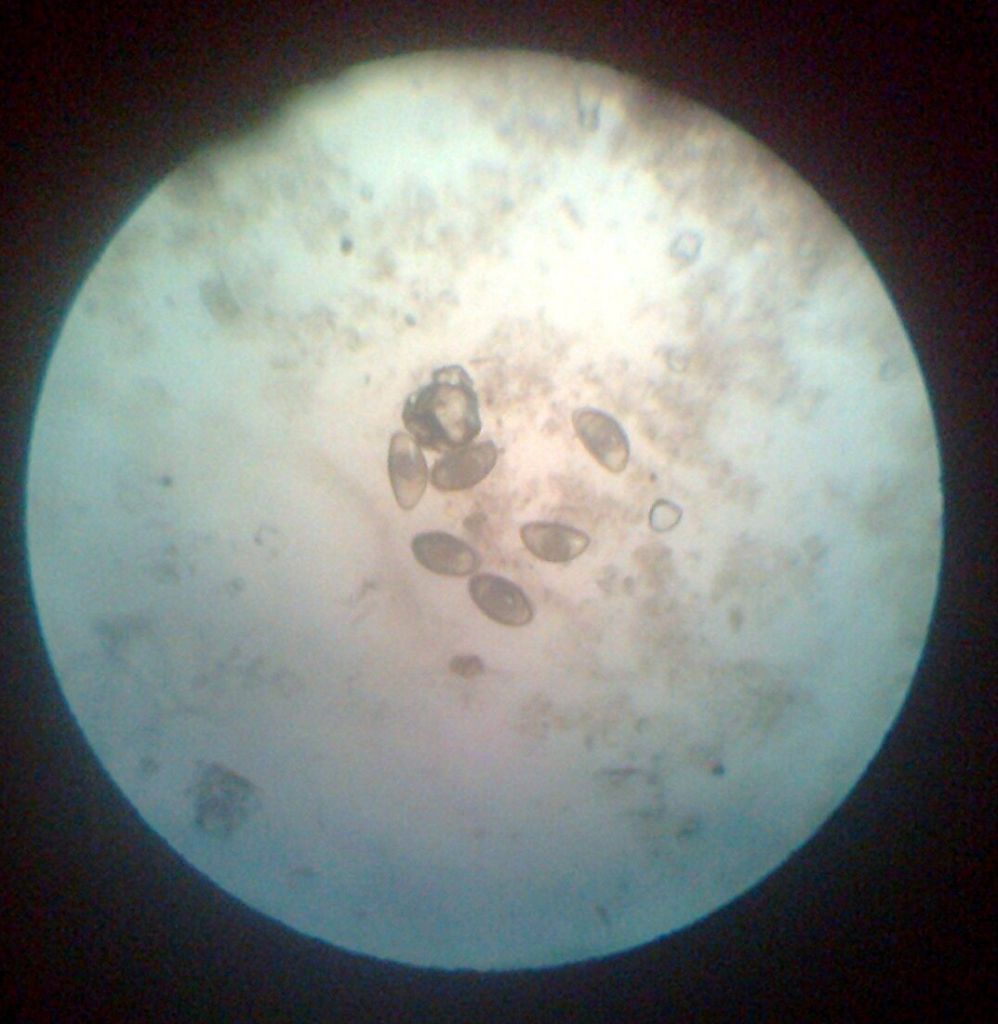

Збудник кокцидиоза під мікроскопом

Застосовується для лікування захворювань, викликаних специфічної флорою у пернатих, кроленят, рогатої худоби і кнурів.